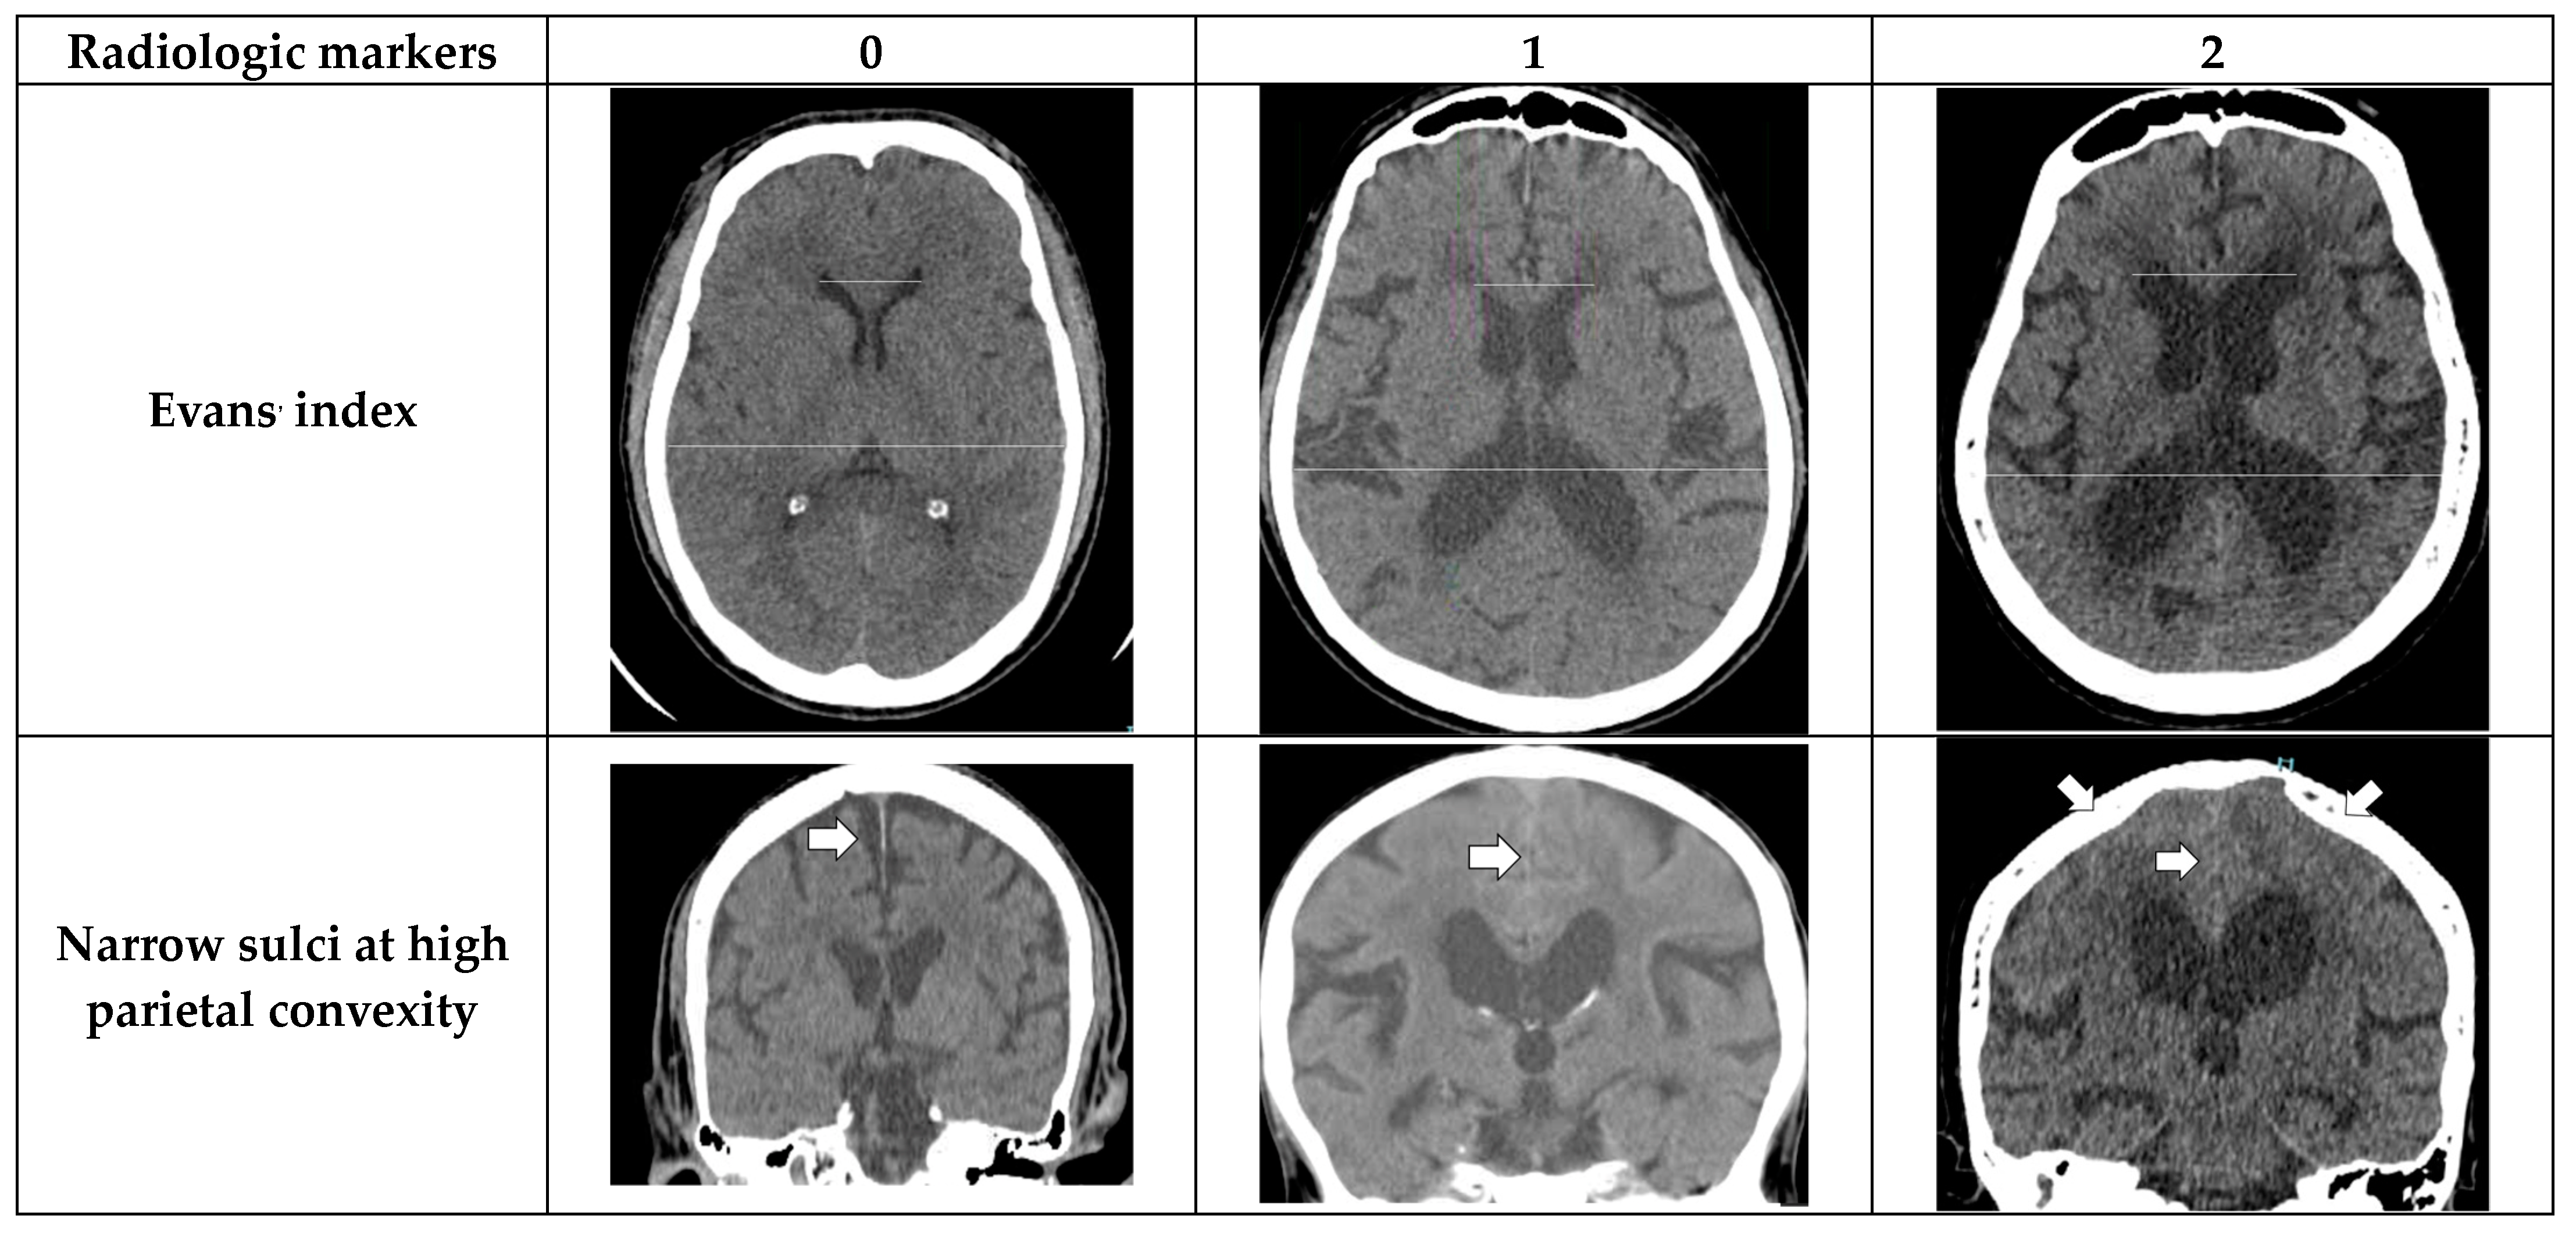

- Evans’ index: The ratio between the maximal width of the frontal horns of the lateral ventricles (B–C) by the maximal width of the inner table of the cranium in the same axial image [9].

- Narrow parietal sulci: At high-convexity and parafalcine region assessed in both axial planes in the most superior slices and coronal plane [10].